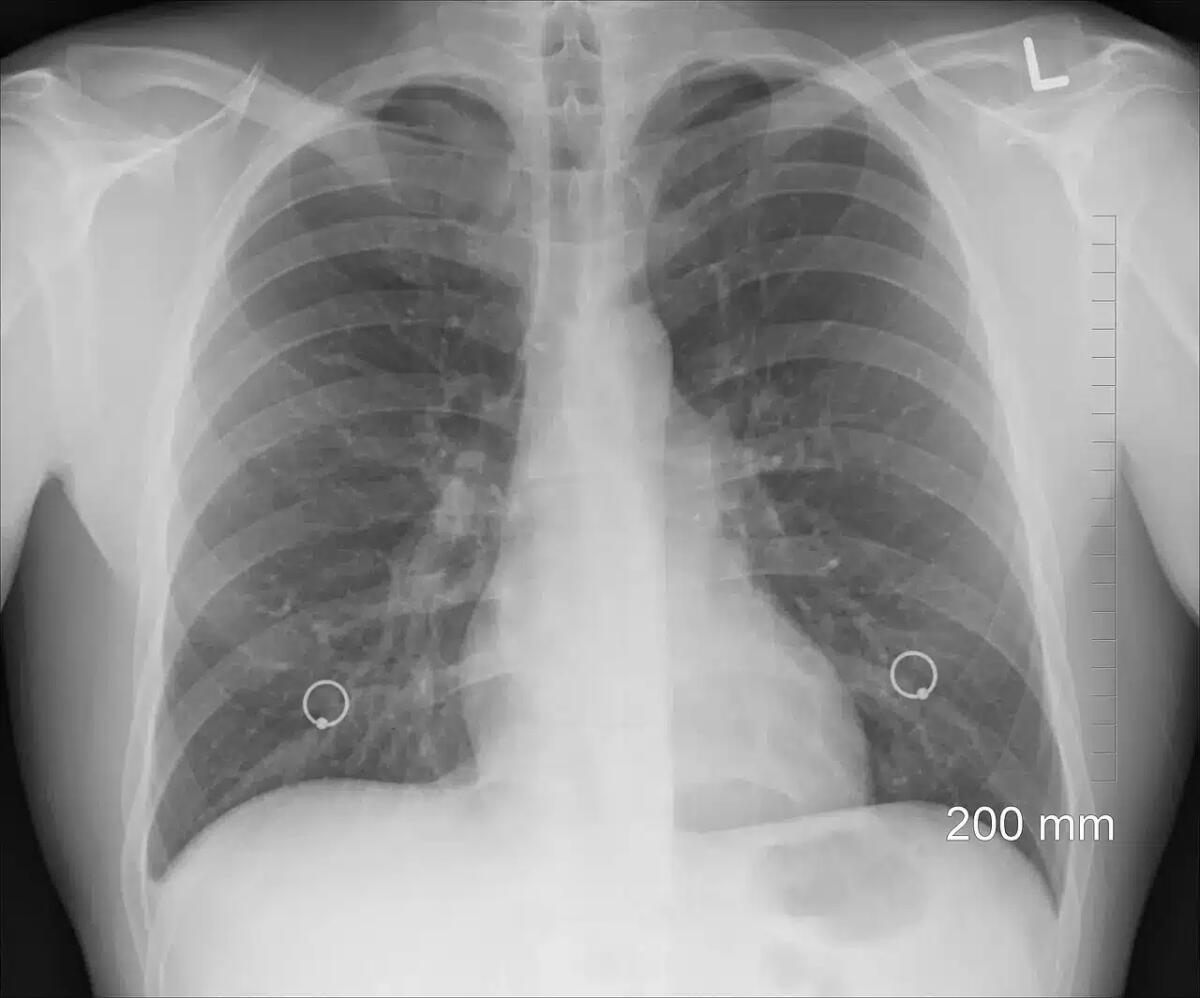

Mantenere i polmoni in salute è essenziale per il benessere generale e la qualità della vita, soprattutto con l’avanzare dell’età.

I polmoni sono organi vitali che permettono al corpo di ricevere ossigeno e di eliminare l’anidride carbonica, ma spesso vengono esposti a inquinanti, fumo e altri fattori che ne compromettono il funzionamento.

Per gli anziani, che possono essere più vulnerabili alle malattie respiratorie, è fondamentale adottare misure preventive e ricevere un supporto adeguato.

I controlli periodici con il medico rappresentano un’opportunità per monitorare la salute polmonare e identificare precocemente eventuali problematiche: gli esami specifici, come la spirometria, possono misurare la capacità respiratoria e diagnosticare condizioni come l’asma o la BPCO.